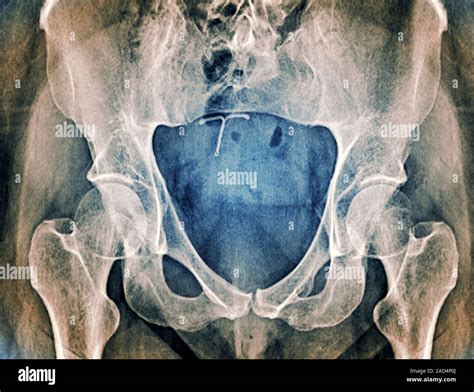

Understanding the intricacies of the sacrum and coccyx is crucial for diagnosing and treating various spinal conditions. One of the most effective diagnostic tools for examining these areas is the Sacrum Coccyx X Ray. This imaging technique provides detailed views of the sacrum and coccyx, helping healthcare professionals identify fractures, dislocations, and other abnormalities. This blog post will delve into the importance of Sacrum Coccyx X Ray, its procedure, interpretation, and common findings.

Sacrum Coccyx X Ray is a vital diagnostic tool for evaluating the sacrum and coccyx. This imaging technique uses low-dose radiation to produce detailed images of the bones, allowing healthcare professionals to identify various conditions. Some of the key reasons for performing a Sacrum Coccyx X Ray include:

Interpreting Sacrum Coccyx X Ray results requires expertise in radiology. Healthcare professionals look for various signs and abnormalities in the images. Some common findings include:

• Fractures: Visible breaks or cracks in the sacrum or coccyx

• Dislocations: Misalignment of the sacrum or coccyx

• Degenerative changes: Wear and tear of the bones, often seen as bone spurs or narrowing of the joint spaces

• Tumors: Abnormal growths or masses in the bone

• Infections: Signs of bone infection, such as osteomyelitis